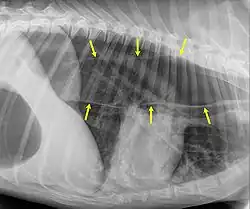

Megaesophagus, also known as esophageal dilatation, is a disorder of the esophagus in humans and other mammals, whereby the esophagus becomes abnormally enlarged. Megaesophagus may be caused by any disease which causes the muscles of the esophagus to fail to properly propel food and liquid from the mouth into the stomach (that is, a failure of peristalsis). Food can become lodged in the flaccid esophagus, where it may decay, be regurgitated, or be inhaled into the lungs (leading to aspiration pneumonia).[1]

An important distinction in recognizing megaesophagus is the difference between when a dog regurgitates or vomits. When a dog regurgitates there is usually not as much effort involved as when a dog vomits. Often when regurgitating, the dog will tip its head down and the liquid and/or food will almost appear to "spill out" of its throat.

One of the primary dangers to a dog with megaesophagus is aspiration pneumonia. Because the food stays lodged in the throat, it can often be inhaled into the lungs causing aspiration pneumonia. One way to avoid this is to make sure that every time the dog eats or drinks anything, that the dog sits for at least 10 minutes afterward or is held in a sitting up or begging position. This disorder has a guarded prognosis, however, a successful management technique is vertical feeding in a Bailey chair.[8]